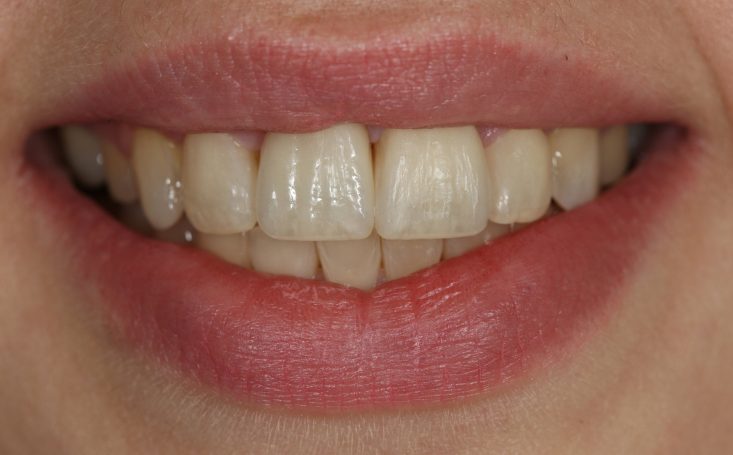

Teleskopierende Oberkieferbrücke mit Vorher- und Nachher-Situation des Patienten.

Teleskopierende Oberkieferbrücke. Wie die eigenen Zähne, aber einfach zu reinigen.